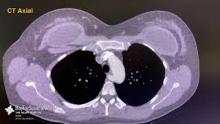

This video demonstrates the technique of robotic assisted division of an aberrant retroesophageal right subclavian artery utilizing a right-sided approach. The patient is a 37-year-old with a history of chest pain and dysphagia. CTA of chest demonstrated an aberrant retroesophageal right subclavian artery (ARSA). The esophagus was effaced at the level of the vessel. The left subclavian had its origin near the right subclavian, and it was felt that endoluminal graft exclusion of the right subclavian artery could not be accomplished without also excluding the left subclavian. The aberrant right subclavian artery was stapled at its origin freeing the entrapped esophagus. The right arm was not revascularized. The patient was discharged home on the 1st postoperative day. Follow-up demonstrated a warm right arm with a weak right radial pulse. There was intermittent right arm fatigue, but no paresthesias. The patient’s dysphagia had completely resolved. CTA on follow-up demonstrated flush division of the right subclavian artery with excellent collateral flow to the subclavian and vertebral arteries. There was no esophageal narrowing or effacement. The right-sided approach offered excellent exposure of the aberrant artery allowing division at its origin from the aorta. In addition, the robotic approach offers improved vision and a stable platform resulting in reduced pain, hospital length of stay and enhance patient recovery time.